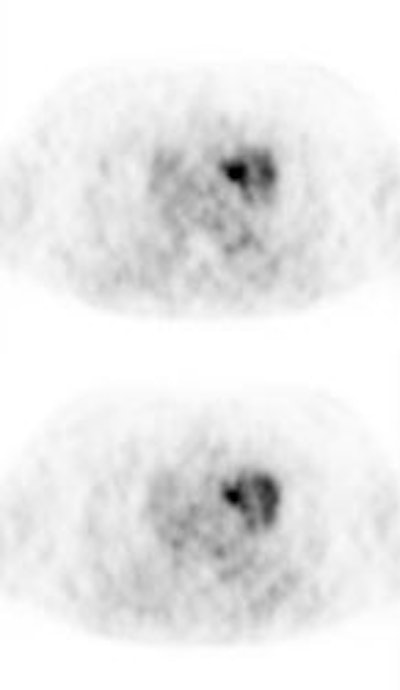

True negative PET scan: The patient in the scan below had a 1.5 cm left upper lobe nodule (shown below) that could be retrospectively identified on a prior CT scan at which time it measured only 4 mm. A PET scan was performed (below right), but demonstrated no uptake in the lesion (some cardiac activity can be seen more anteriorly). Because the nodule had enlarged from a prior exam, the nodule was resected and found to be a granuloma. Nodules larger than 1.5 cm that are negative on PET scans have a highly likelihood for representing benign or indolent lesions. |